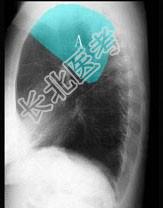

- 单项选择题在图所示正常胸部X线影像图像上,该英文字母所代表的肺段为 ( )

A、尖段

B、后段

C、尖后段

D、舌叶上段

E、前段